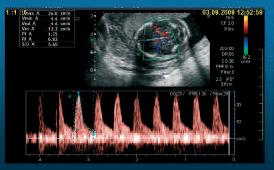

Intrauterinní detekce anemie

- průměr pupečníku (DeVore, 1990)

- tloušťka placenty ( Salzman, 1989)

- obvod sleziny (Oepkes, 1993)

- PSV (Man, 2000)

- nižší viskozita krve vede ke zvýšení rychlosti průtoku

- nejcitlivější metoda využívaná u Rh inkompability

- normogram – MOM (Mari, 2000)

- kordocentéza

- MCA, kolmo na arterii, PSV 3x

- http://www.perinatology.com/calculators/MCA.htm

- anemie: MOM nad 1:32